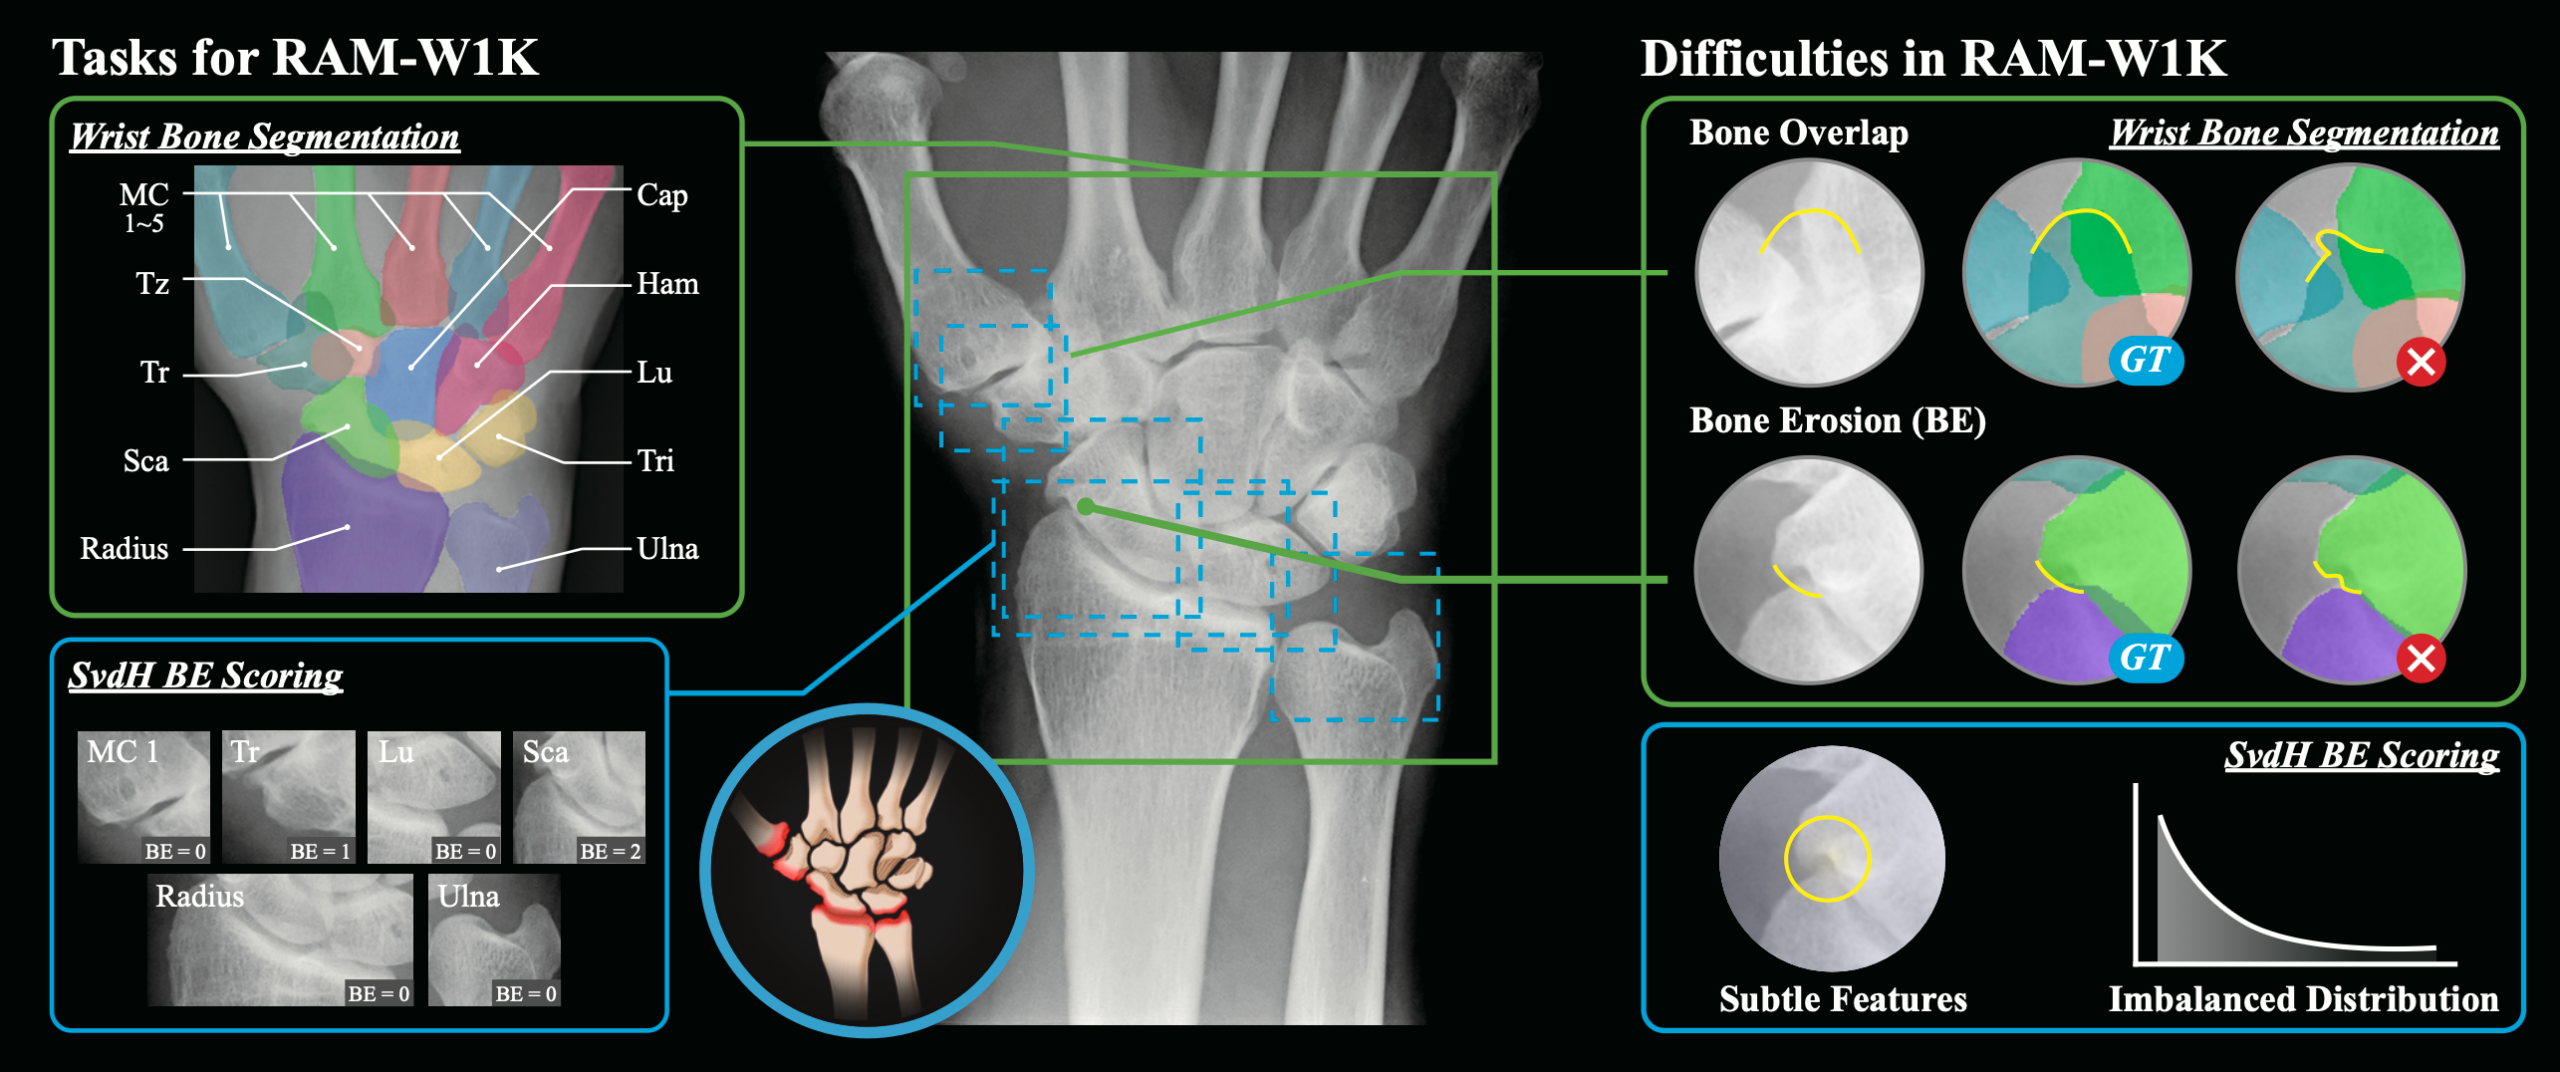

研究チームは手首 X 線画像に基づく初の公的マルチタスクデータセット RAM-W600 を公開しました。対象は 388 名の患者のX線画像 1,048 枚で、618 枚に骨インスタンスセグメンテーション注釈、800 枚に標準的評価法である、Sharp/van der Heijde(SvdH)法による骨びらんスコアが付与されています。さらに、Unet、TransUNet などの代表的な深層学習アーキテクチャや、SAM といった基盤モデルを用いた多様な AI ベンチマーク実験が実施され、性能比較が行われました。